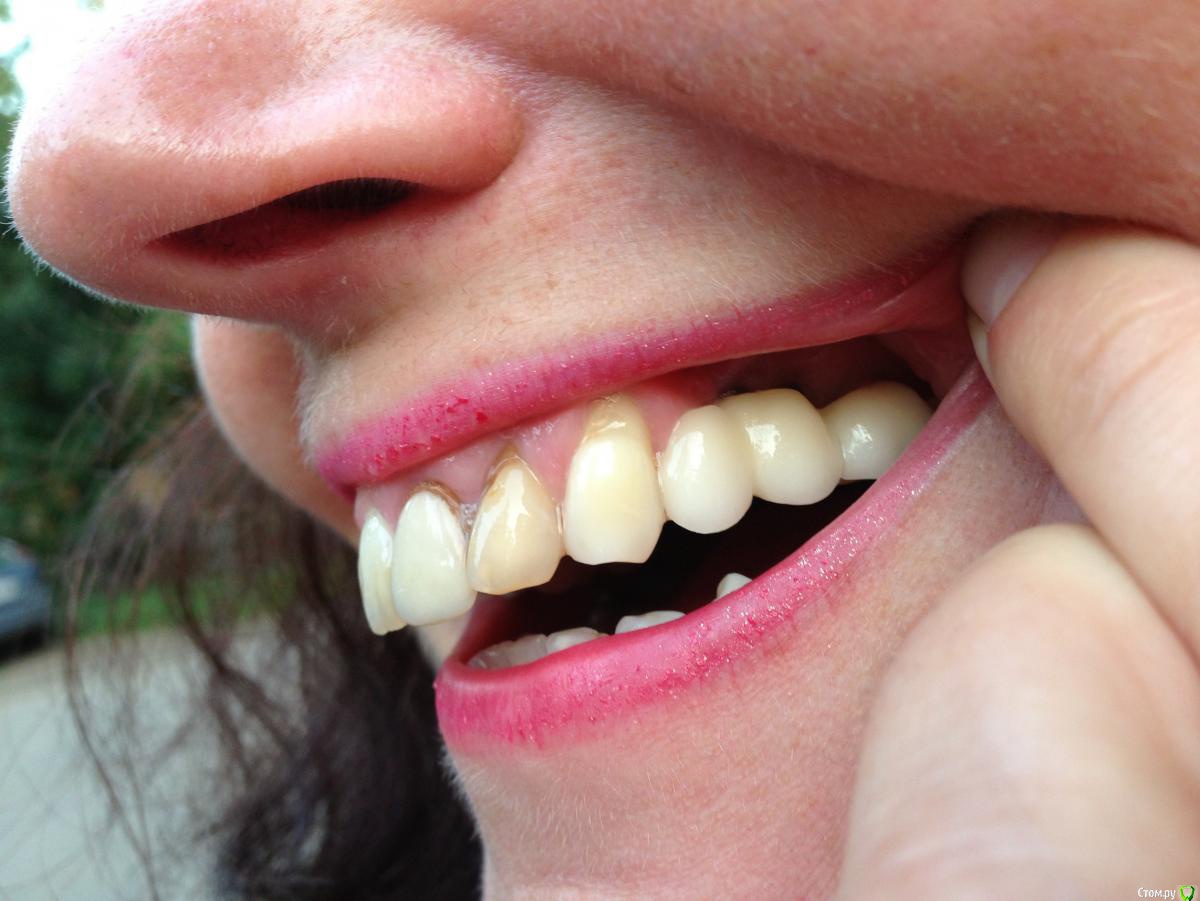

chervoncevdaniil Опубликовано 2 февраля, 2018 Поделиться Опубликовано 2 февраля, 2018 Мягких тканей действительно там маловато Ссылка на комментарий

Bier Опубликовано 2 февраля, 2018 Поделиться Опубликовано 2 февраля, 2018 и мягких тканей мало и снимок бы посмотреть... 2 Ссылка на комментарий

Oks72 Опубликовано 4 февраля, 2018 Автор Поделиться Опубликовано 4 февраля, 2018 Мягких тканей действительно там маловато и мягких тканей мало и снимок бы посмотреть... Снимка после установки имплантов к сожалению нет. Имеется только КТ, сделанная перед их установкой. отдельные коронки после открытого синус лифтинга как то вообще нецелесообразно, скорей всего еще и концевой дефект По поводу отдельных коронок понятно. Концевого дефекта (если я правильно поняла его значение) не было - родная "семерка" была и есть. Доктор уверял меня, то со временем десна будет "стремиться" к коронке, т.к. она изготовлена из диоксида циркония, т.е. безметалловая. Этого не произошло, более того, металлические абатменты в центральной части моста стали видны еще больше. Эстетика при широкой улыбке не радует(. Уважаемые стоматологи, я бы очень хотела услышать ваше мнение - может ли повлиять в моем случае отсутствие десневой пластики на долговечность службы имплантов?Скажем так - риск возникновения проблем и потери имплантов у меня выше или нет? Или не проведение десневой пластики - это нормальная практика? Спасибо! Ссылка на комментарий